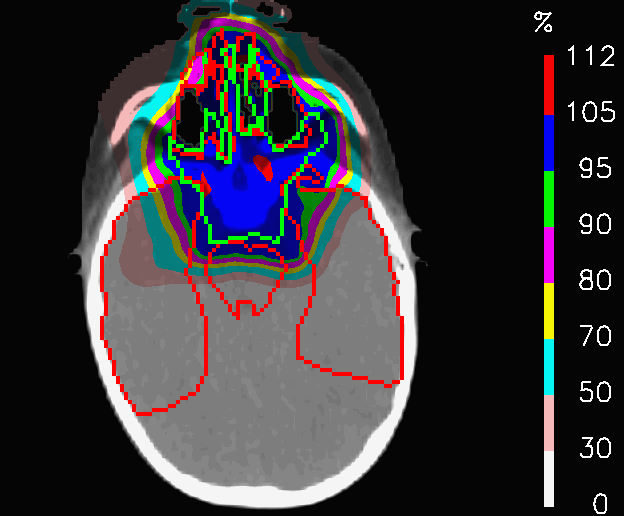

PLAN-OL-2 was conceived with more angularly spaced fields than the original F1, F2, F3, F4; this configuration would have been not feasible without the OL penalization, since the tough constraints of the rod safety margins would have prevented a homogeneous coverage of the target volume, leading necessarily to underdosed areas in the periphery of the CTV and high dose peaks in the middle. Fig.9 shows the dose distributions of PLAN-NOM and PLAN-OL-2, whereas results are summarized in tables 2. Despite the fact the increase of 𝐕𝟏𝟎𝟎subscript𝐕100\mathbf{V_{100}} is less accentuated in PLAN-OL-2 than in PLAN-OL-1, the improved target coverage is visible in the comparison of the cumulative DVHs of the CTV in Fig.10, whereas no difference was noticeable in the cumulative DVH of PLAN-OL-1 compared to PLAN-NOM. This new field configuration provides a remarkable sparing of the left and right parotis and the brainstem at the cost of decreasing the improvement concerning the myelon.

Refer to caption

(a) PLAN-NOM

(b) PLAN-OL-1

Figure 9: Patient with metallic cage: dose distributions for the nominal plan and the one re-computed with OL penalization, choosing new fields more angularly spaced (+10°) with respect to those used for the nominal plan.